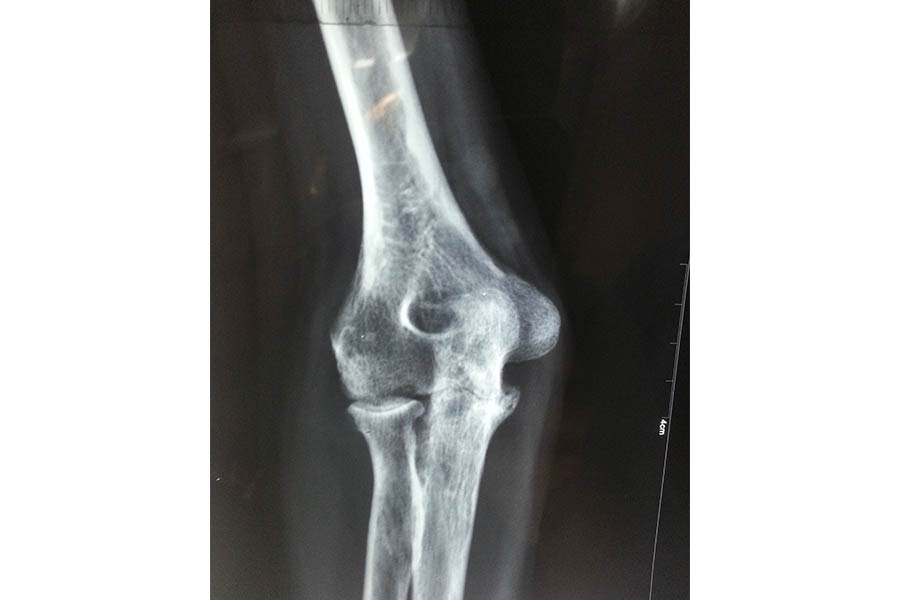

Total Elbow Replacement

Case 1